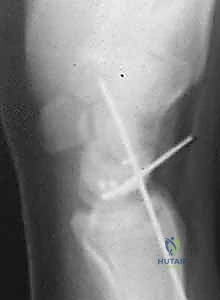

* An AP intraoperative fluoroscopic image demonstrating precise Kirschner wire placement across the scaphocapitate joint and the reduced scapholunate joint. Suture anchors are visible in the scaphoid at the dorsal SLIL footprint.

* A lateral intraoperative fluoroscopic image confirming accurate Kirschner wire placement and the reduced scapholunate joint. Note the suture anchors in the scaphoid.